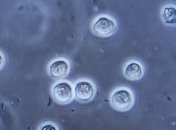

Ученые впервые сняли на видео смерть лейкоцита.